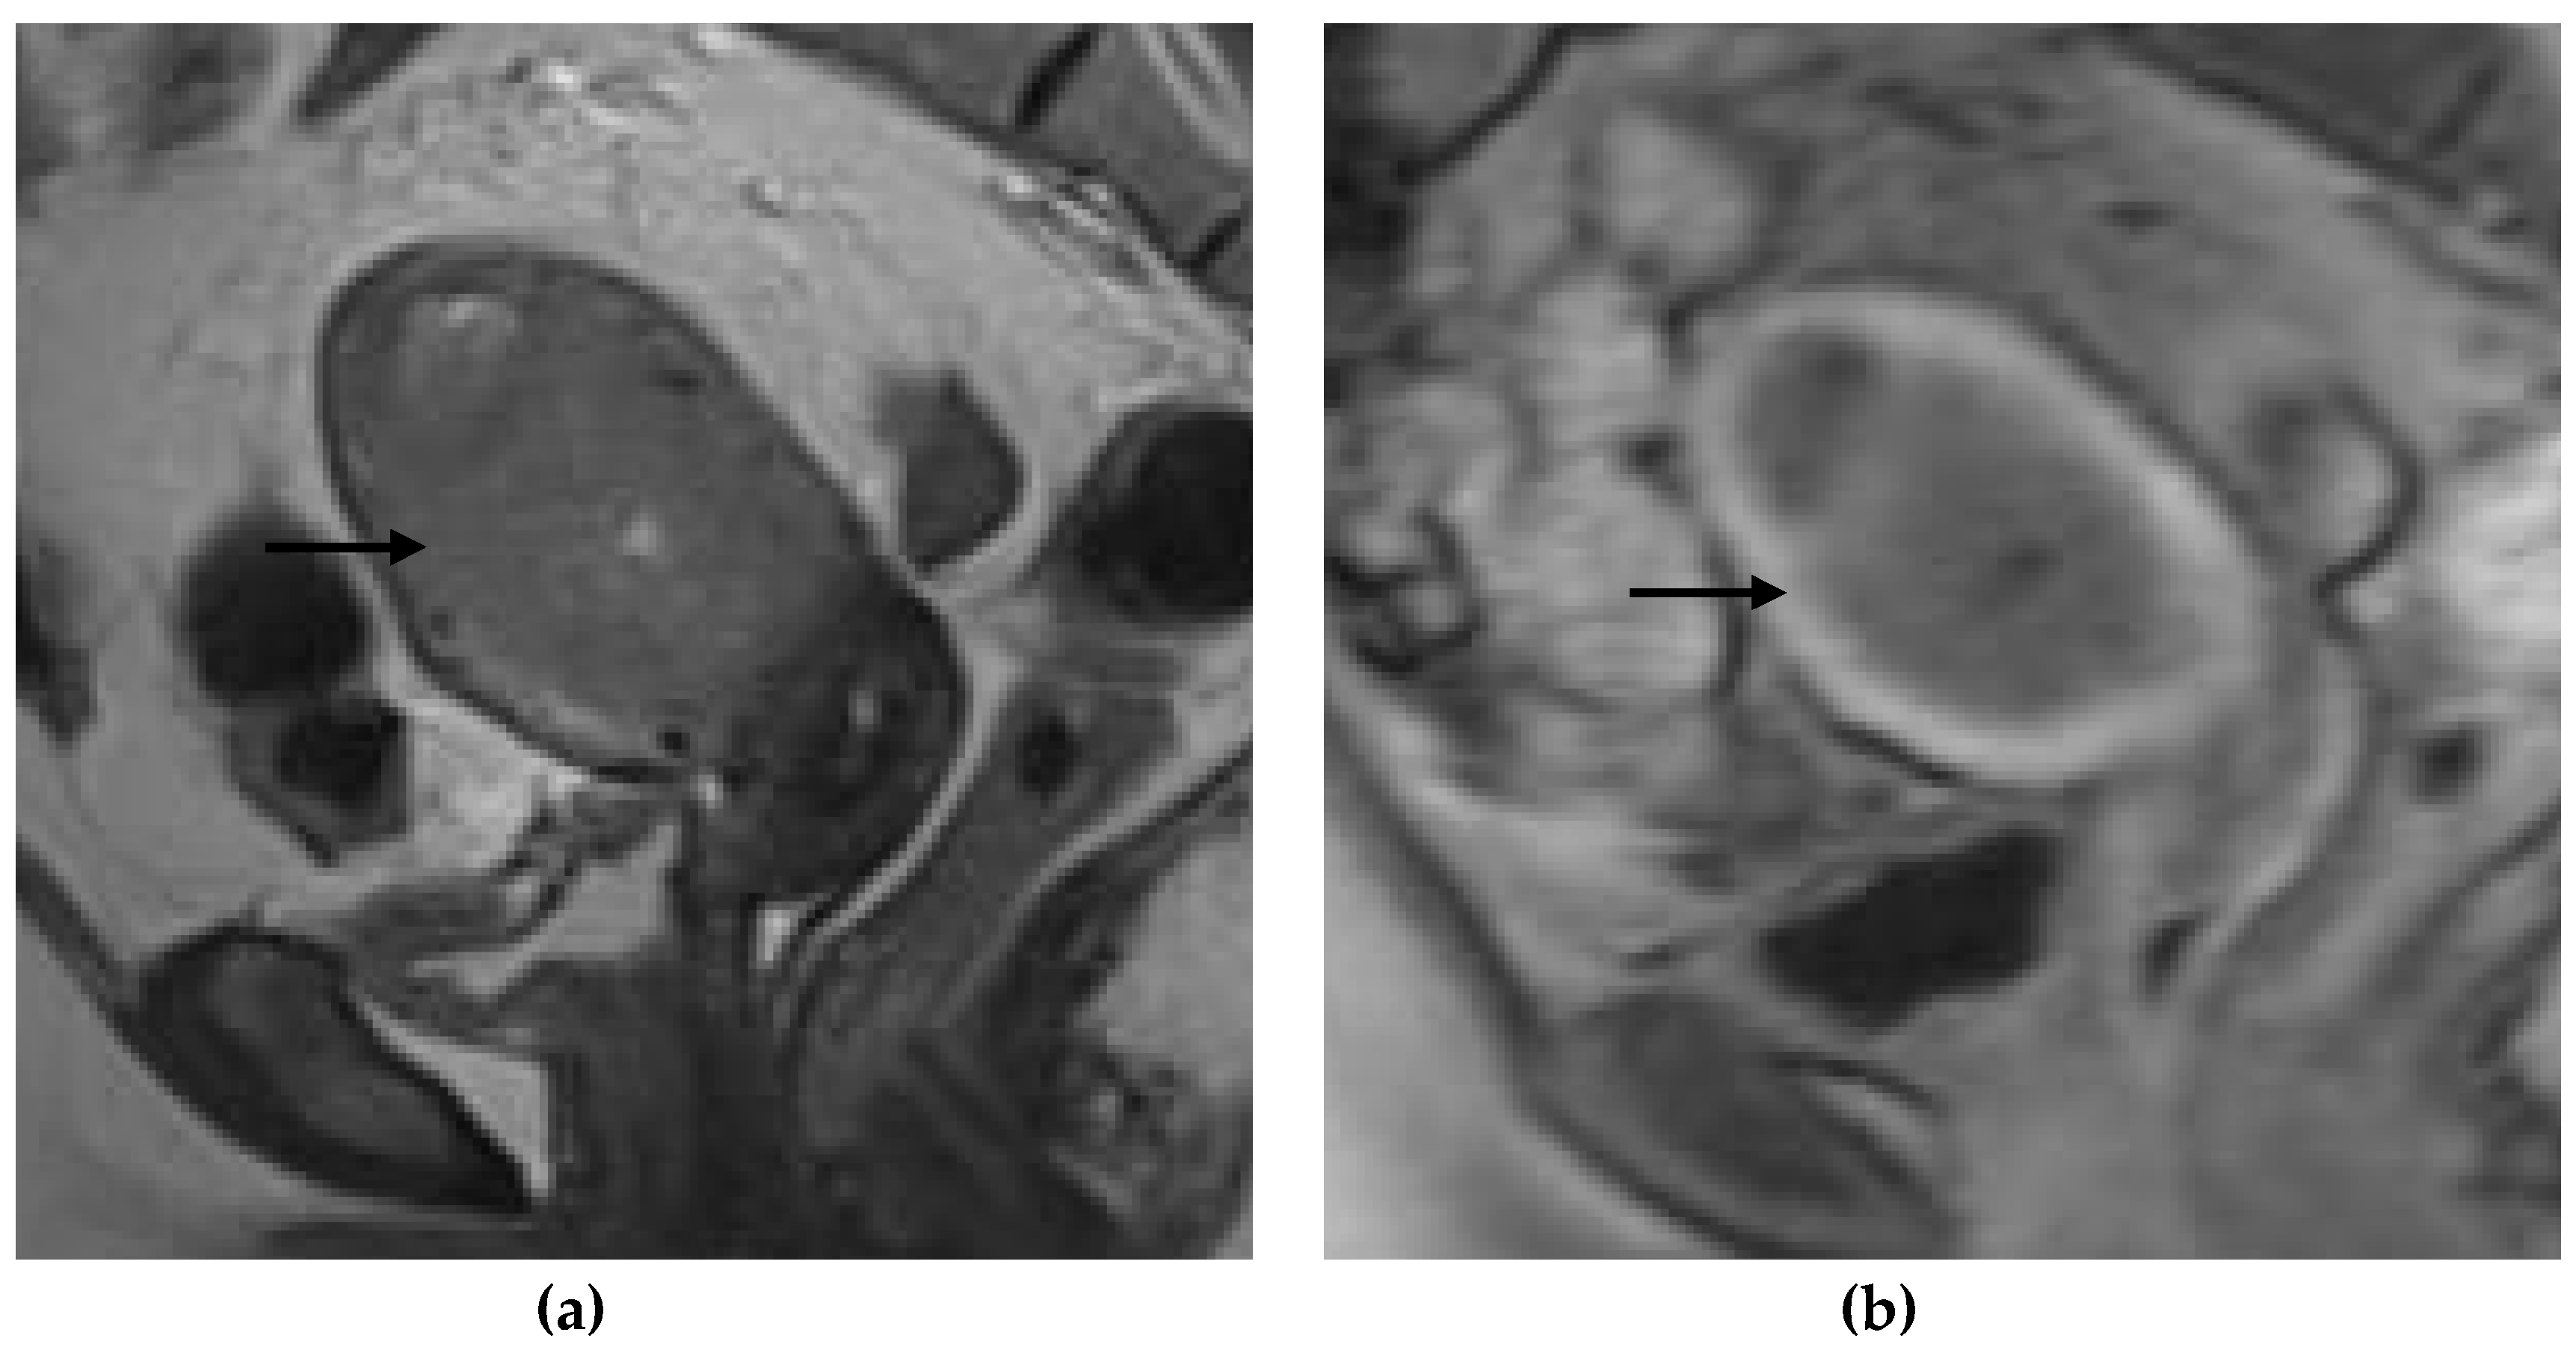

Figure 1, Figure 2, Figure 3 and Figure 4 depict the representative MRI images of tumors with < 50% myometrial invasion and ≥50% myometrial invasion, as well as the representative combined T2WI+DCE-MRI images for false-positive and false-negative cases, respectively. The diagnostic performance of MRI in predicting the depth of myometrial invasion is presented in Table 2 and Table 3. The depth of myometrial invasion (any depth) was correctly determined in 75% (n = 24) and 78% (n = 25) of cases on T2WI and DCE-MRI alone, respectively, whereas the percentage increased to 91% (n = 29) of cases when the T2W images were read together with those obtained by DCE-MRI.

Figure 2. Representative MRI images of endometrial carcinoma with ≥50% myometrial invasion. (a) Axial T2WI, (b) sagittal T2WI, and (c,d) sagittal DCE-MRI images during the early (c) and late (d) acquisition stages. Tumors (arrow) with ≥50% myometrial invasion presented as iso- to mildly hyperintense on T2WI compared to the myometrium (a,b) with disruption of the junctional zone. On DCE-MRI, the tumors appeared as hypointense masses compared to the adjacent myometrium with interrupted subendometrial enhancement (SEE) (c), irregular tumor-to-myometrium interface, and extension of the tumor beyond the outer half of the myometrium (d). Abbreviations: MRI, magnetic resonance imaging; dynamic contrast-enhanced magnetic resonance imaging (DCE-MRI); T2WI, T2-weighted imaging; subendometrial enhancement (SEE).